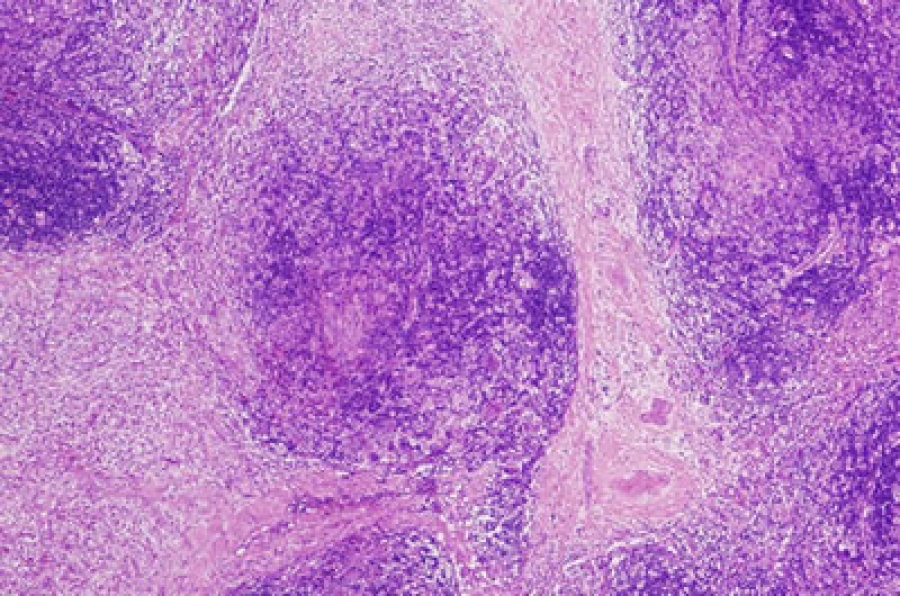

Según datos de la Lymphoma Coalition, cerca de 735 mil nuevos casos se registran anualmente en todo el mundo. En este contexto, la detección temprana desempeña un papel crucial en el éxito terapéutico y refuerza la importancia tanto de las campañas de concientización como del avance de las investigaciones dirigidas al desarrollo de terapias más eficaces.

Con este objetivo, QIAGEN, empresa alemana especializada en diagnóstico molecular, ofrece QIAseq, una tecnología en la que se basan paneles de secuenciación para el estudio de linfoma . La solución permite trazar el perfil molecular de los tumores, identificar fusiones génicas, mutaciones puntuales y patrones de expresión, además de proporcionar información detallada sobre el desarrollo de la enfermedad y las vías biológicas implicadas.